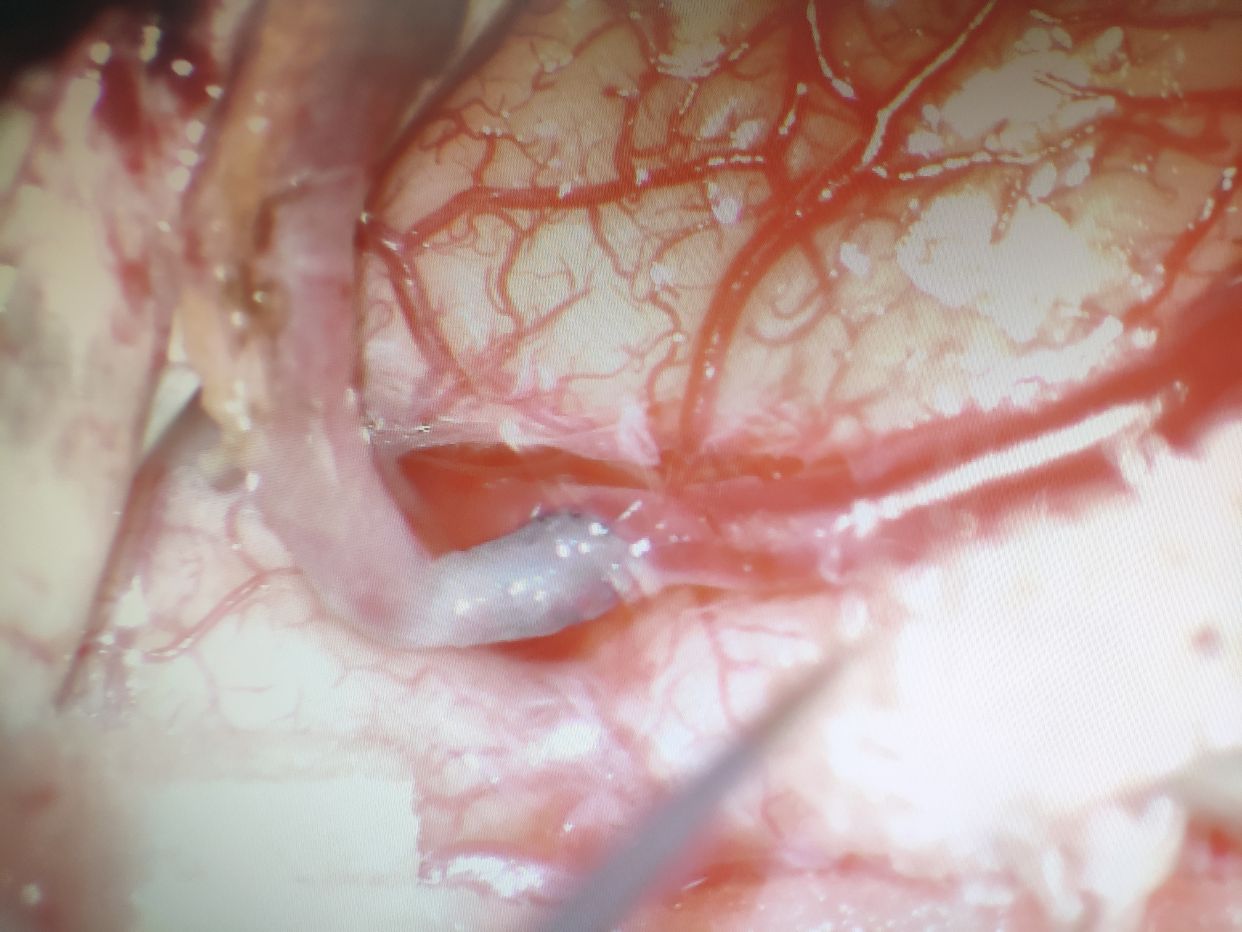

完善术前准备后行右侧颞浅动脉-大脑中动脉搭桥术

游离颞浅动脉,修剪,亚甲蓝染色

大脑中动脉M3受体血管准备完成

10-0丝线端侧吻合后,吻合口通畅。